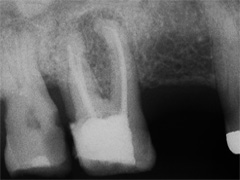

2 Aufnahmen sind von 2002 und die dritte vom 01.11.2010

Als Zufallsbefund entdeckter, bis dahin beschwerdefreier apikaler Prozess an Zahn 36. Dessen insgesamt stark verengtes Innenraumsystem gestattete damals in erster Sitzung nur die Darstellung von 2 Kanälen. Wenn intensivstes Weitersuchen erfolglos bleibt, ist dem erfahrenen Behandler irgendwann zumindest so viel über den fehlenden Kanal bekannt: Er kann nicht sehr grosslumig sein und die Weitersuche auf den nächsten Termin zu verschieben ist nicht sehr riskant. Oft genug erlebt, gelingt dann frisch mindreseted und brainrebooted das in Sekunden, was zuvor in 20 min nicht gelingen mochte. So auch hier geschehen, bei der Suche nach dem 3. Kanal.